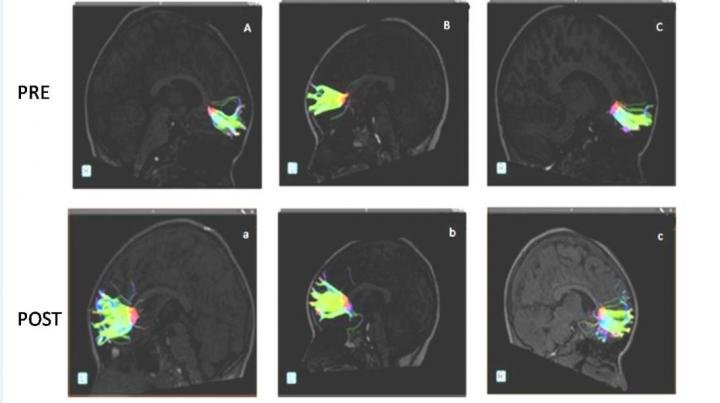

Fibers belonging to the greater forceps pre-musical training are observed (A, B, C). Fibers belonging to the same patients after 9 months of musical training are observed below (a, b, c). Credit: Radiological Society of North America

An advanced MRI technique (DTI or “diffusion tensor imaging”) was used to scan their brains before and after music lessons, which took nine months.  DTI can identify microstructural changes in the brain’s white matter

The study revealed improvement in connections after the nine months of studying music.  Water molecules moved along the fibers better and the fibers themselves were longer, most significantly in the “minor forceps” – a part of the frontal cortex of the brain, which was associated with autism in prior studies.